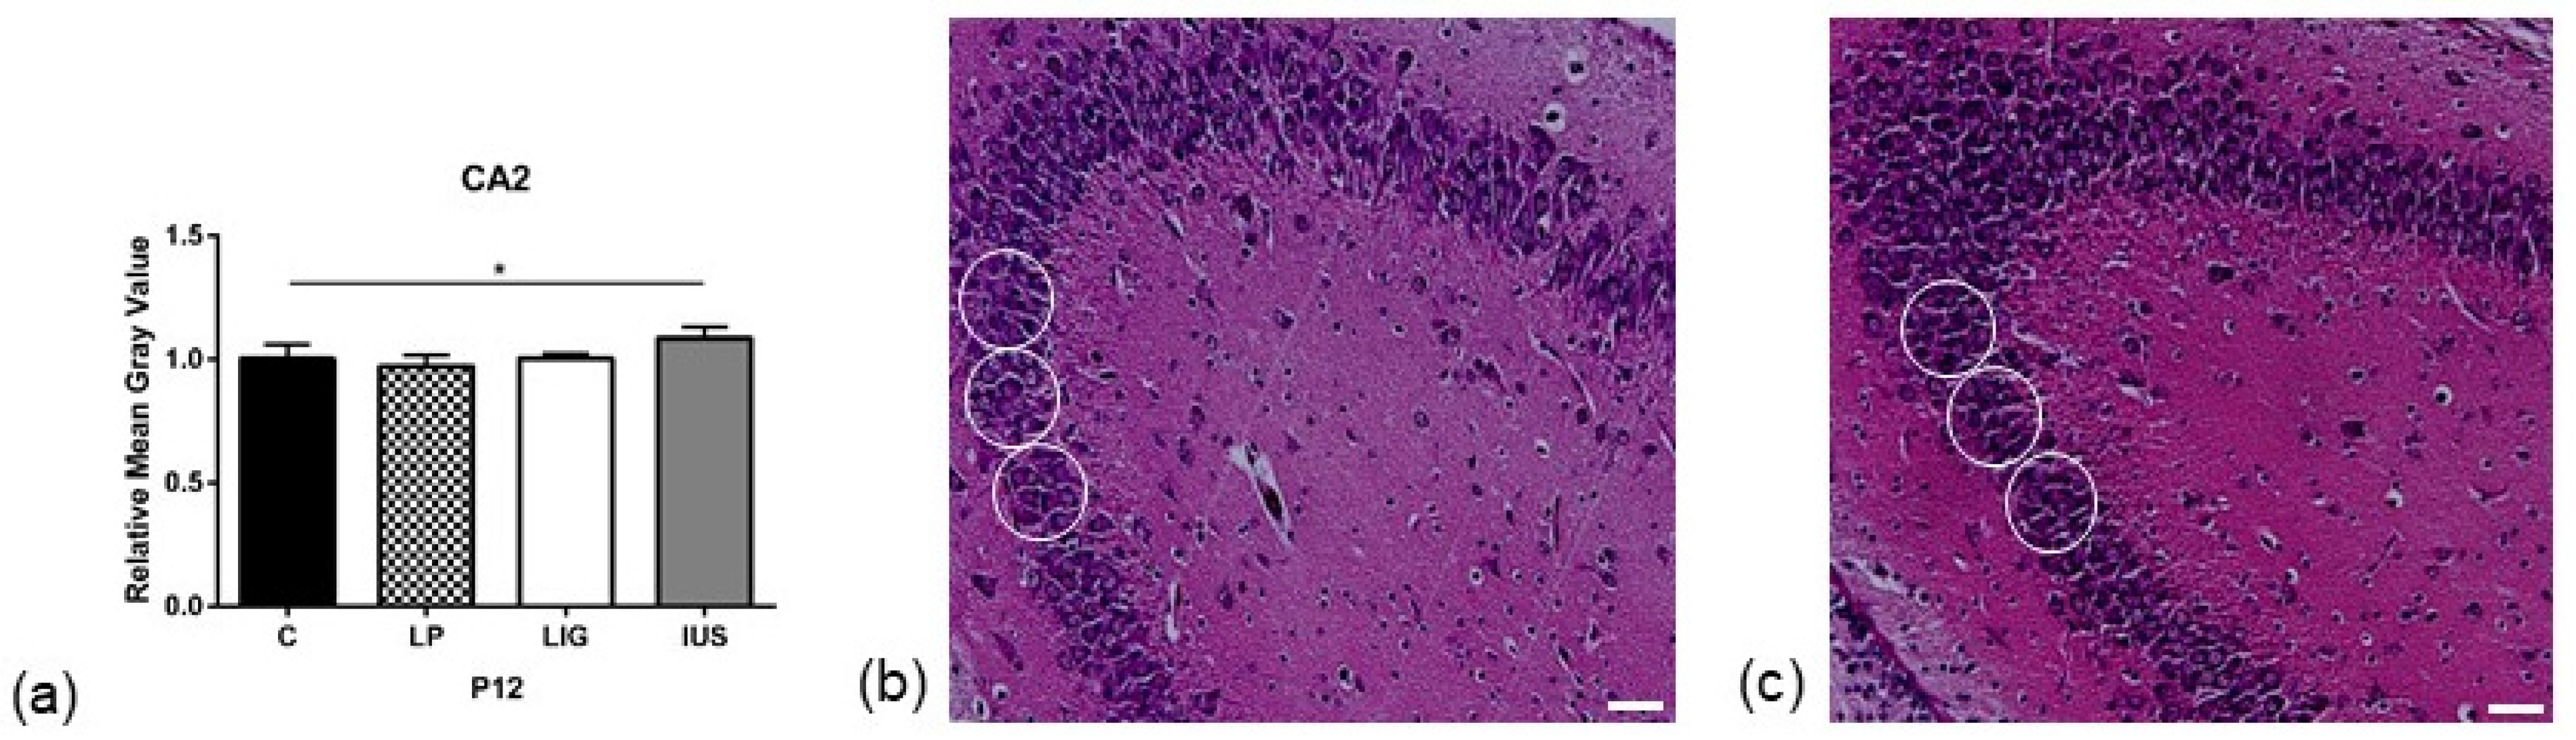

On PND 1, we did not find any significant alterations to cell densities in the hippocampal subregions studied (Table S1). On PND 12, we found a significantly decreased cell density in the molecular dentate gyrus (MoDG) hippocampal subregion of LP offspring (C, 1.00 ± 0.02; LP, 0.90 ± 0.04; LIG, 0.94 ± 0.06, IUS, 1.03 ± 0.07) (Figure 2, Table S1) as well as a significantly increased cell density in the cellular CA2 hippocampal subregion of IUS offspring (C, 1.00 ± 0.06; LP, 0.97 ± 0.04; LIG, 1.00 ± 0.02, IUS, 1.09 ± 0.05) (Figure 3, Table S1).

Figure 3.

(a) Results of cell density analysis in the cellular CA2 subregion of the hippocampus on postnatal day PND 12 (C, n = 5; LP, n = 7; LIG, n = 6; IUS, n = 7). For each animal, grayscale measurements were performed at three replicates per hippocampal region. All data were normalized to the mean of the control group (C). Representative images of cell density measurement of (b) control (C) offspring and (c) offspring after intrauterine stress (IUS) in the cellular CA2 subregion of the hippocampus on postnatal day PND 12 (HE staining, 20-fold magnification). White circles indicate regions of interest (ROIs) used for quantitative analysis. Scale bar = 50 μm. Asterisks indicate significance; *, adjusted p < 0.05.

In contrast, IUS pups presented with increased hippocampal cell densities. Interestingly, we found significantly increased cell densities in the CA2 region, which was neither affected in LP nor LIG offspring. Thus, perinatal stress can be considered as an independent risk factor for region-specific changes in neuronal development [57,58,59,60]. Stress may also be a compensating factor with respect to hippocampal proliferation in situations impairing proliferation, such as placental insufficiency, which may explain the absence of significantly reduced cell densities in our LIG offspring group.